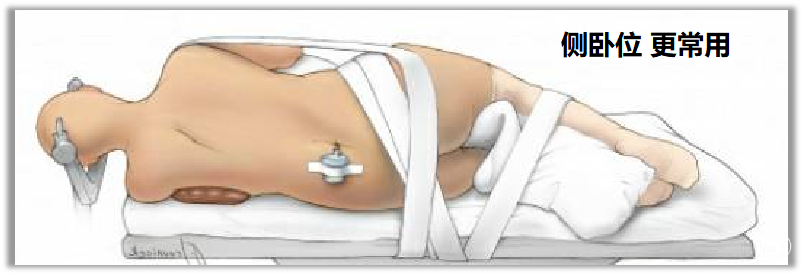

▼2.体位

通常采用健侧俯卧位,腋下垫起,头部下垂15°并向健侧旋转10°,颈部稍前屈,使下颌距胸骨约2横指,患侧乳突与手术台面大致平行并位于最高位置。患侧肩部用肩带轻拉向床尾端,使颈肩角>100°,确保手术操作不受肩部阻挡影响,需注意不可牵拉过重,以免造成臂丛神经损伤。

成人以头架固定,亦可用胶带将头位固定在床台,可无需头架固定。